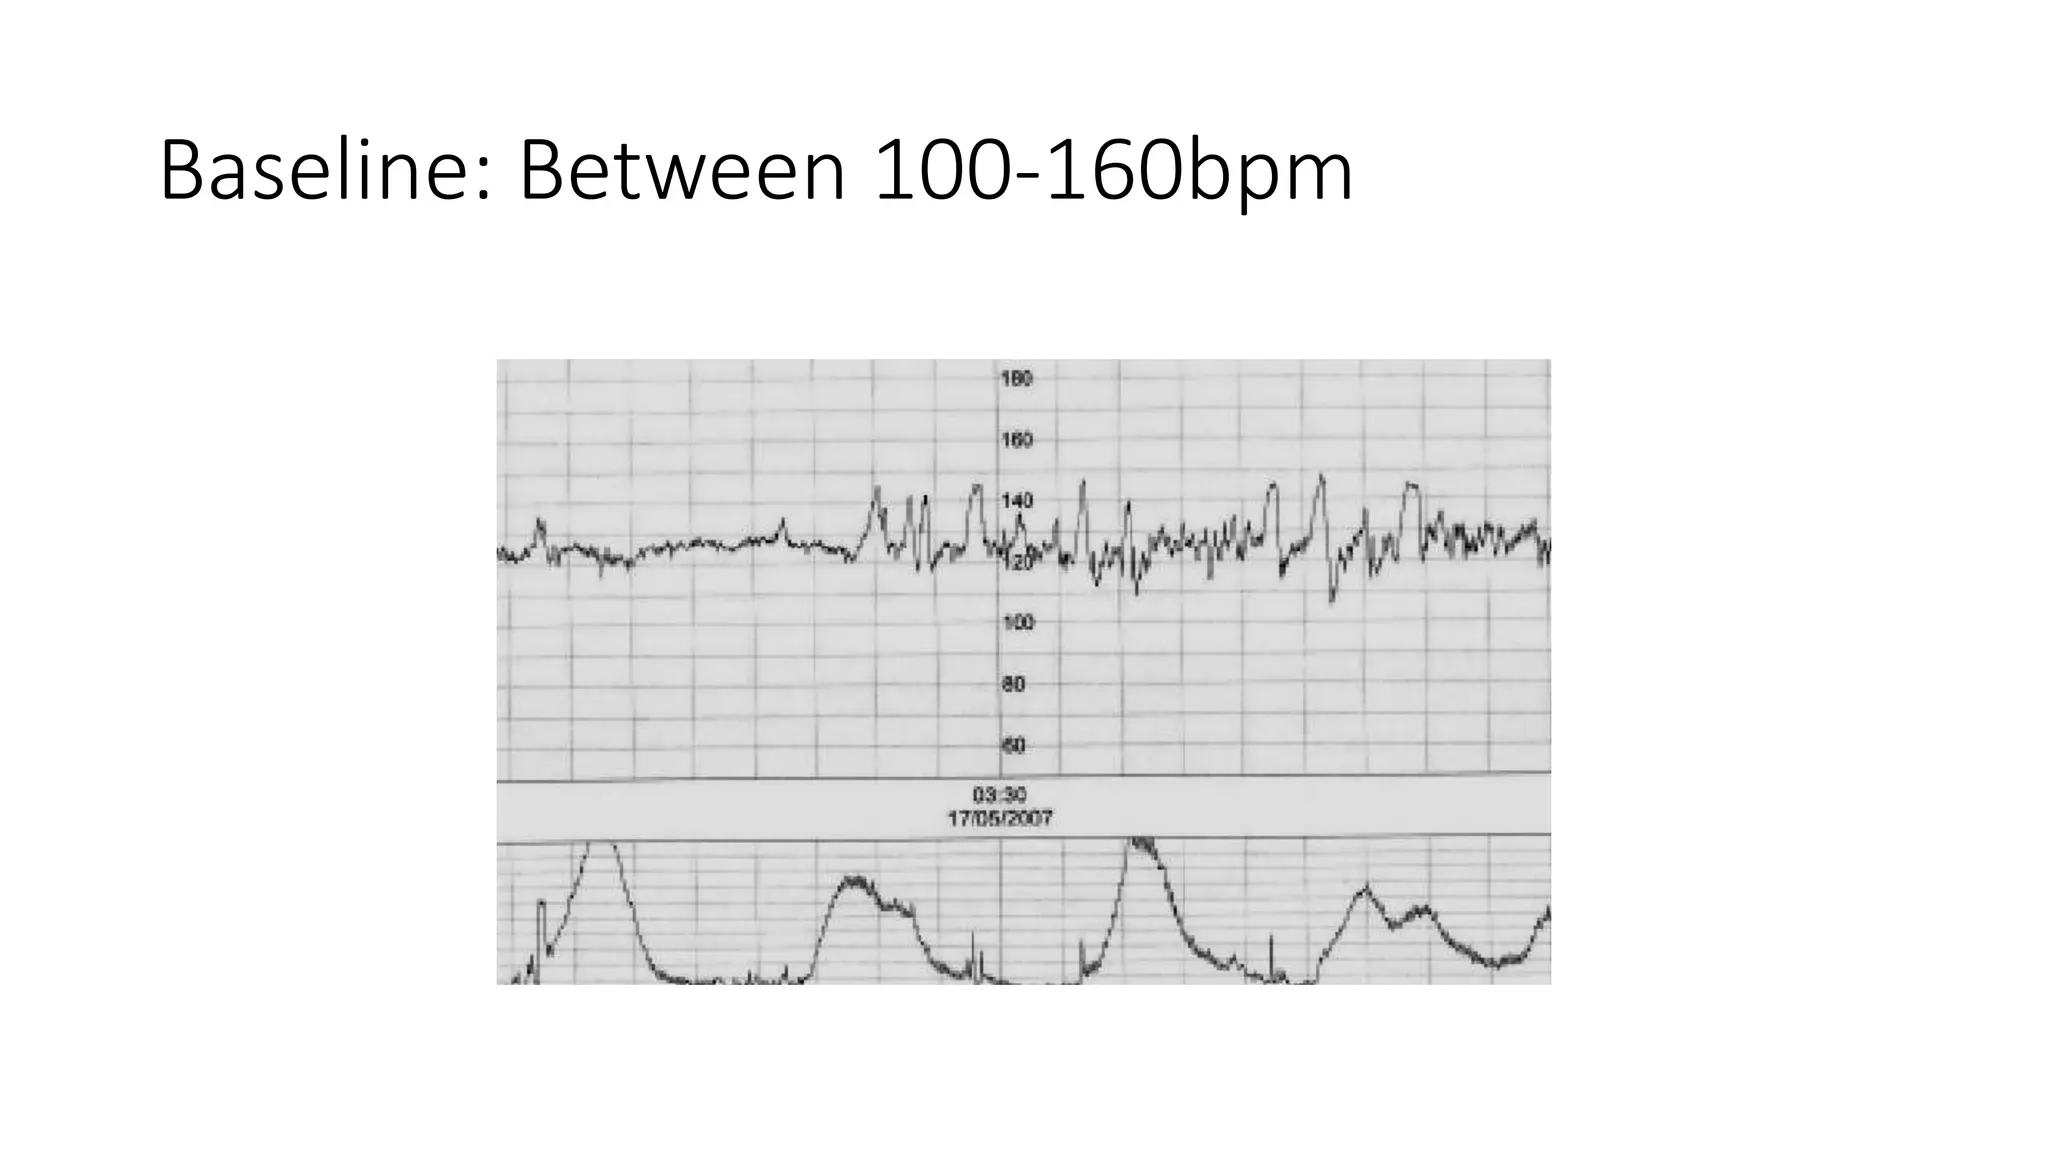

The document discusses key metrics for monitoring a baby's heart rate in utero, including the normal baseline rate of 100-160 bpm and variability. It also covers types of accelerations and decelerations that can occur, such as early or late, as well as bradycardia, which is an abnormally slow heart rate.